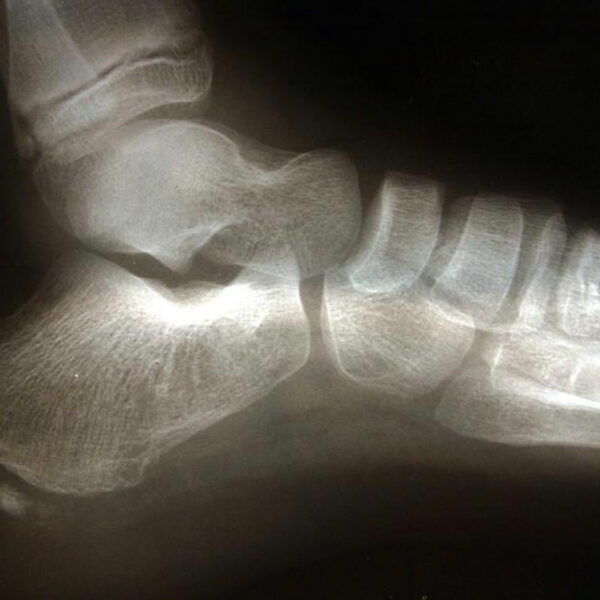

Commonly affecting athletes who frequent activities include running and jumping, heel spur is caused due to calcium deposits on the underside of the heel bone. The symptoms include inflammation of tissues and tendons near the spur, pain while walking or jogging, formation of calluses, swelling or redness of the affected part of the heel. The pain that is experienced is often sharp and stabbing. Sometimes that pain can go away to be replaced by a dull throbbing that aggravates while doing activities such as walking, jumping, jogging, or running.